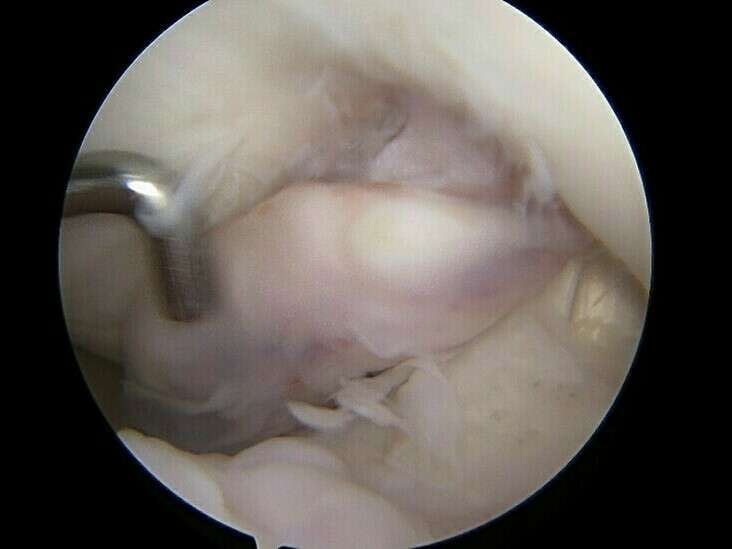

En l’absence d’évolution spontanément favorable, le traitement est systématiquement chirurgical et consiste à retirer ce nodule d’arthro-fibrose sous arthroscopie au cours d’une hospitalisation de courte durée en Chirurgie Ambulatoire. Lors de l’intervention chirurgicale, le chirurgien s’assurera de la récupération de l’extension complète du genou.

Le diagnostic de cette lésion se fait par la recherche de signes cliniques évocateurs et par l’IRM qui retrouve généralement un nodule à la face antérieure de la plastie ligamentaire au niveau de l’échancrure inter-condylienne sur lequel vient buter la trochlée fémorale.